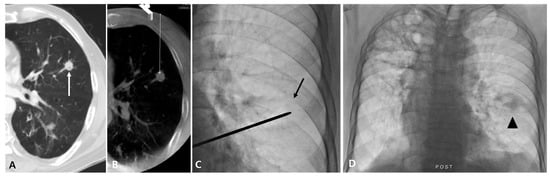

Figure 2.

Case of fluoroscopy-guided PTNB with the aid of planning CBCT of a lung nodule in a 79-year-old man with lung metastatic adenocarcinoma that resulted in a complication. A diagnostic CT image (A) and planning CBCT image (B) show an 11 mm nodule (white arrow) in the left upper lobe with a long aerated lung length achieved by needle insertion (46 mm). A lesion depth was 75.6 mm (white dashed line). On fluoroscopy, the nodule is identifiable (black arrow) (C), and PTNB was performed twice. After PTNB, hemoptysis occurred, and a post-PTNB fluoroscopic image shows peritumoral consolidation, representing a hemorrhage (arrowhead) (D).